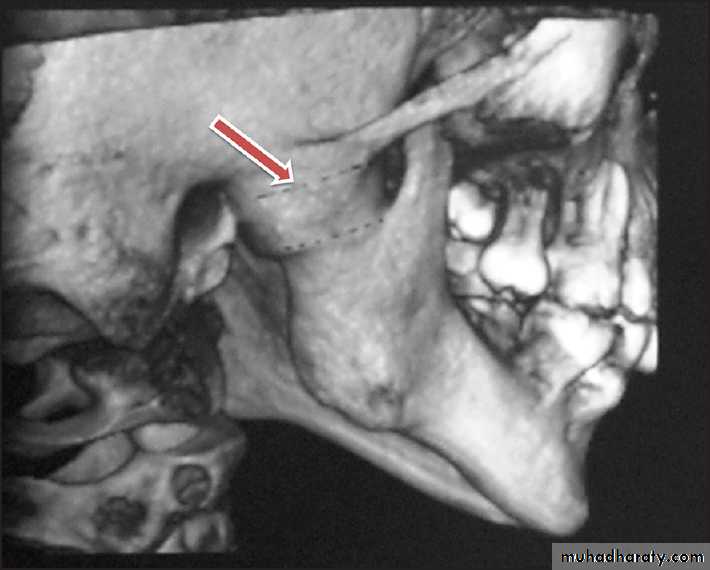

Joint Reconstruction

Dr. Mohammed Amjed Alsaegh, 202132

Ankylosis

21. What are the indications for total joint reconstruction?

• Fibrous or bony ankylosis with severe anatomic abnormalities• Severe inflammatory disease, such as rheumatoid arthritis, that results in anatomic mutilation of the joint components and functional destabilization

• Failed autogenous grafts in multiply operated patients

• Destruction of autogenously grafted tissues by pathology